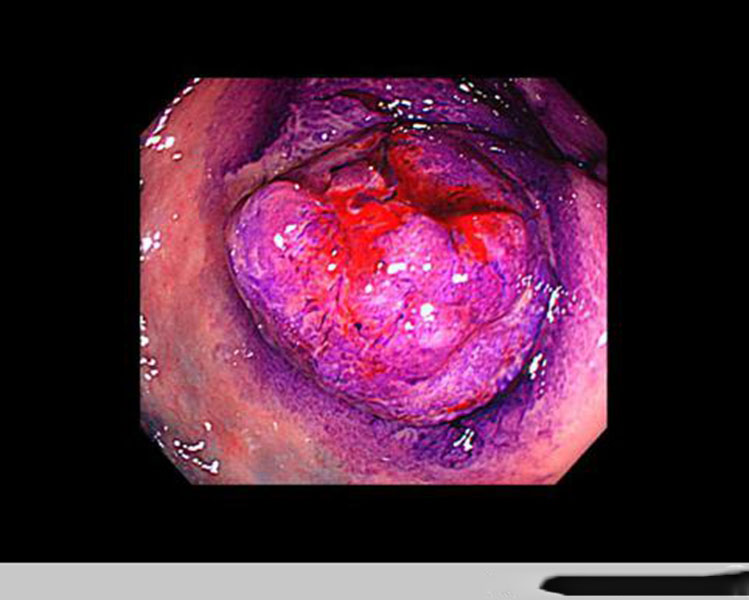

直腸腫瘤